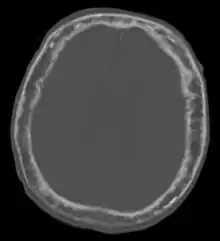

![]() | |

"This 92 year-old male patient presented for assessment of sudden inability to move half his body. An incidental finding was marked thickening of the calvarium. The diploic space is widened and there are ill-defined sclerotic and lucent areas throughout. The cortex is thickened and irregular. The findings probably correspond to the 'cotton wool spots' seen on plain films in the later stages of Paget’s disease." | |